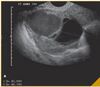

27a, dor vulvar ha 2 dias, caroco doloroso Sem febre G0 Ao EF, a imagem 1. Atendimento 2. Exames solicitados 3. HD 4. Passo a passo para a drenagem

Apresentar-se (nome e funcao) 1. Bartholinite ou abscesso da glandula de Bartholin 2. Drenagem local Analgesia com AINE Antibiotico 3. lavar as maos, paramentacao Antissepsia Anestesia com lidocaina Incisao na pele Expressao e divulsao da lesao irrigacao com SF0.9% Nao indicar sutura